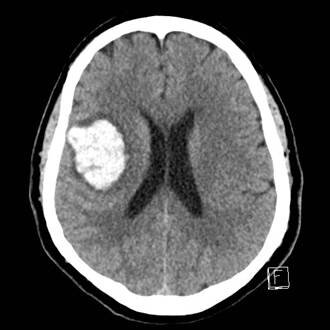

Corbin was in the back of his house when he realized something was terribly wrong. He would later learn that an artery in his brain had burst, a condition called intracerebral hemorrhage, which is fatal in about half of all cases. Corbin didn’t understand what was happening, but he was determined to get help.

Corbin's brain bleed was big and dangerous. He says his doctors were amazed he survived it.

Corbin was rushed to MUSC Health, where doctors saw that he’d suffered the most debilitating type of stroke. They had to try to remove the blood expanding deep in his brain. Traditional surgery would carry the risk of damaging more brain tissue, because the neurosurgeon would have to make a large window in the skull and dissect healthy tissue to reach the blood that had pooled in the head.

But there was a new option: minimally invasive surgery that requires only a tiny hole in the skull, just large enough to fit a 15-millimeter surgical tool called an obturator that gently parts brain tissue and makes way for the placement of the NICO Brain Path sheath. The obturator is then removed and the sheath acts as a corridor through which the hematoma, or pooled blood, can be removed.